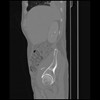

7 CUERPO,CE,Sagittal,3.000,CUERPO,Sagittal,